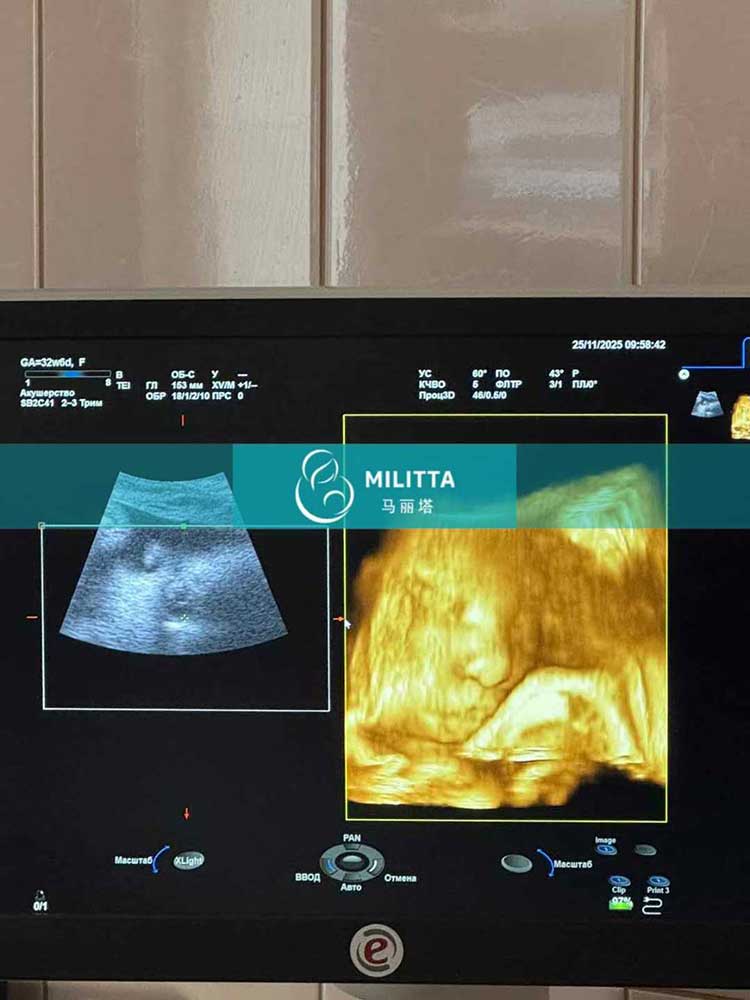

粱夫妇在乌克兰匹配的试管妈妈来妇产医院做孕32周+B超

粱夫妇在乌克兰匹配的试管妈妈来妇产医院做了孕32周+B超,胎儿身体正常发育着,期待小宝宝的健康到来~